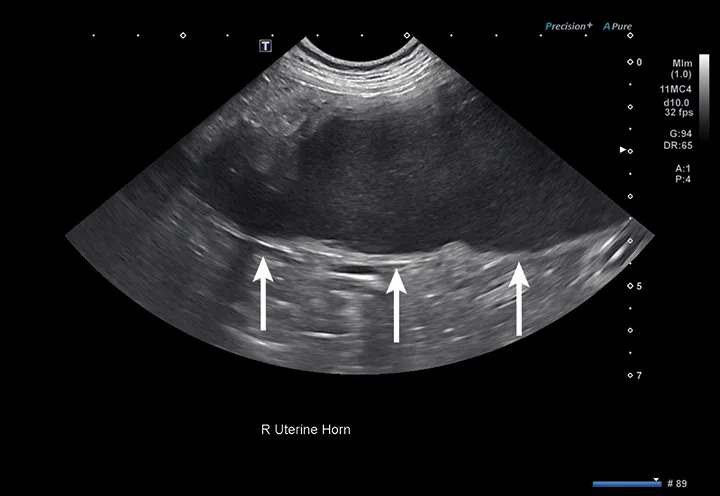

Ultrasound image of an enlarged uterine horn containing hypoechoic fluid in a dog and arrows pointing to the uterine wall.

FIGURE 4

Right uterine horn of a dog with pyometra. The uterine wall (arrows) is too thin to be a normal small intestinal segment.

Pyometra is a reproductive emergency that requires rapid diagnosis and treatment.16 In patients with pyometra, the uterus contains variable amounts of echogenic intraluminal fluid, with varying degrees of dilation and wall thickness.16 Ultrasound findings should be considered in conjunction with patient history, physical examination findings, and laboratory results, as other less common differentials (including mucometra, hydrometra, and hemometra) are also possible.16 Distinct wall layering may be lost in small intestinal segments that are severely dilated; this can be similar in appearance to a fluid-dilated uterus.